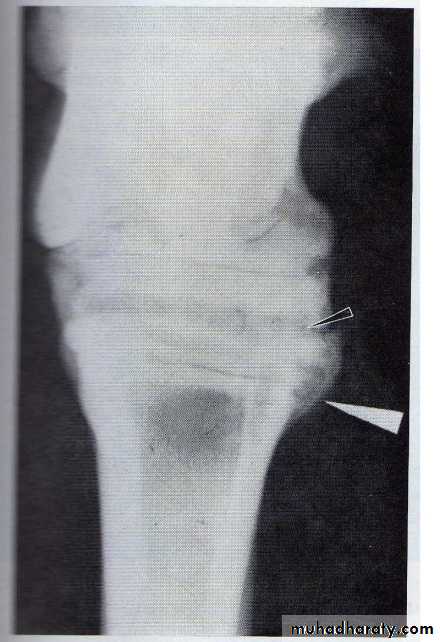

Bone spavin. Black pointer indicates ankylosis of the distal intertarsal joint. The white arrow indicates new bone growth on the medial aspects of the third and central tarsal bones. These are typical changes in bone spavin.

Site of bone spavin on the right hind limb. The arrow indicates the prominence of new bone growth.